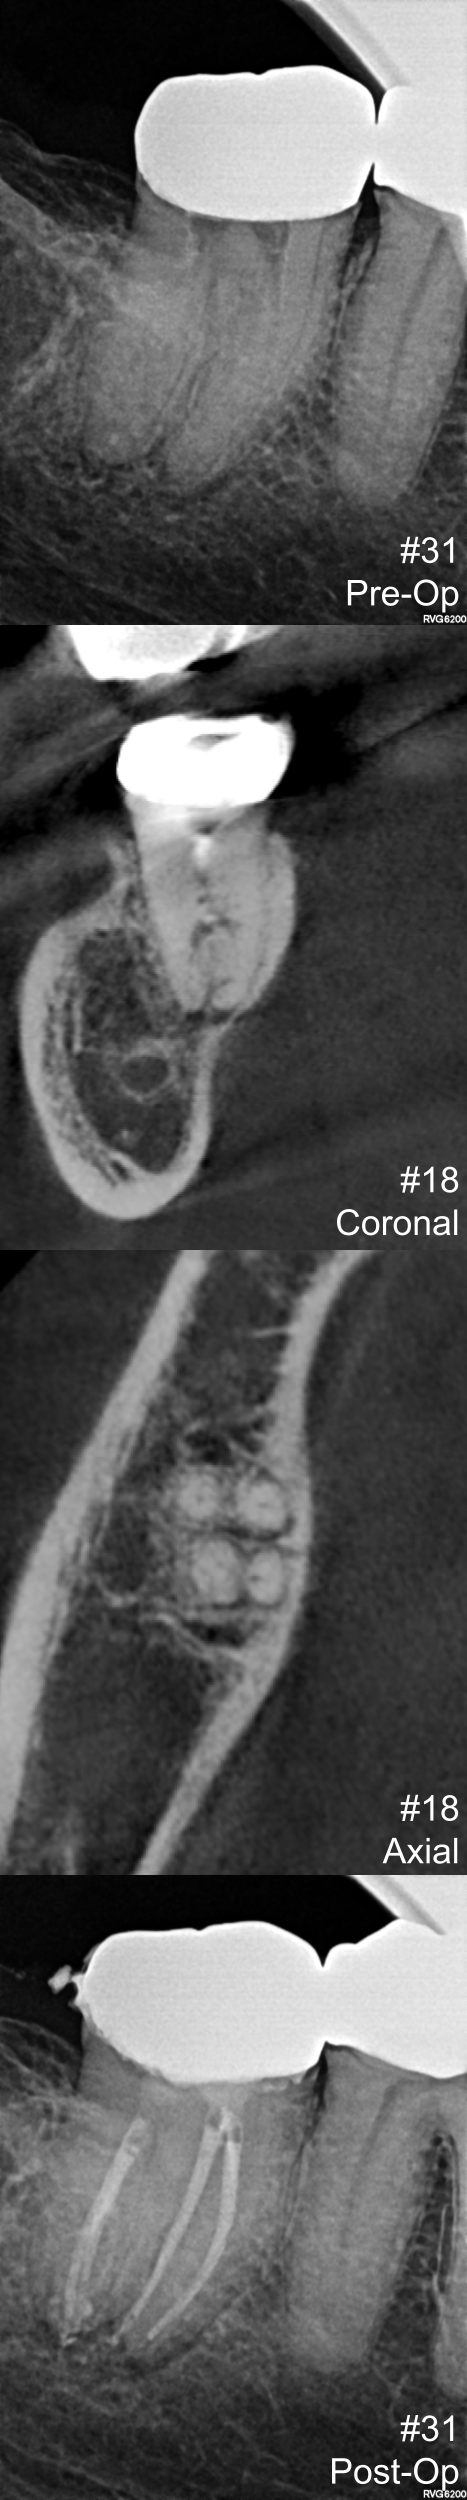

View fullsize